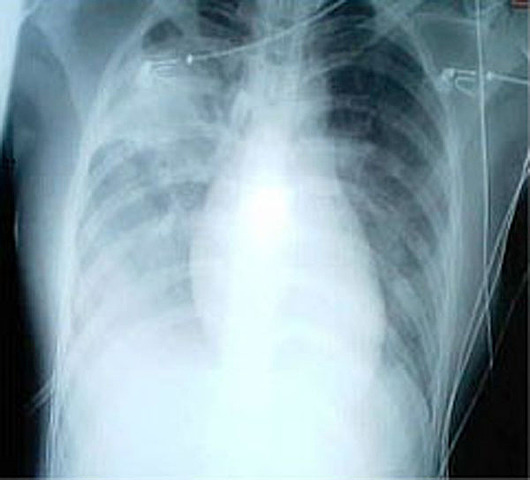

Els símptomes són febre, mal de coll i de cap, tos, dificultats per respirar. I les radiografies mostren elements de la pneumònia en els pulmons. Aquest nou virus té una semblança del 71 % amb els Sars, transmès pels ratpenats. La seva confirmació oficial és de gener de 2020.